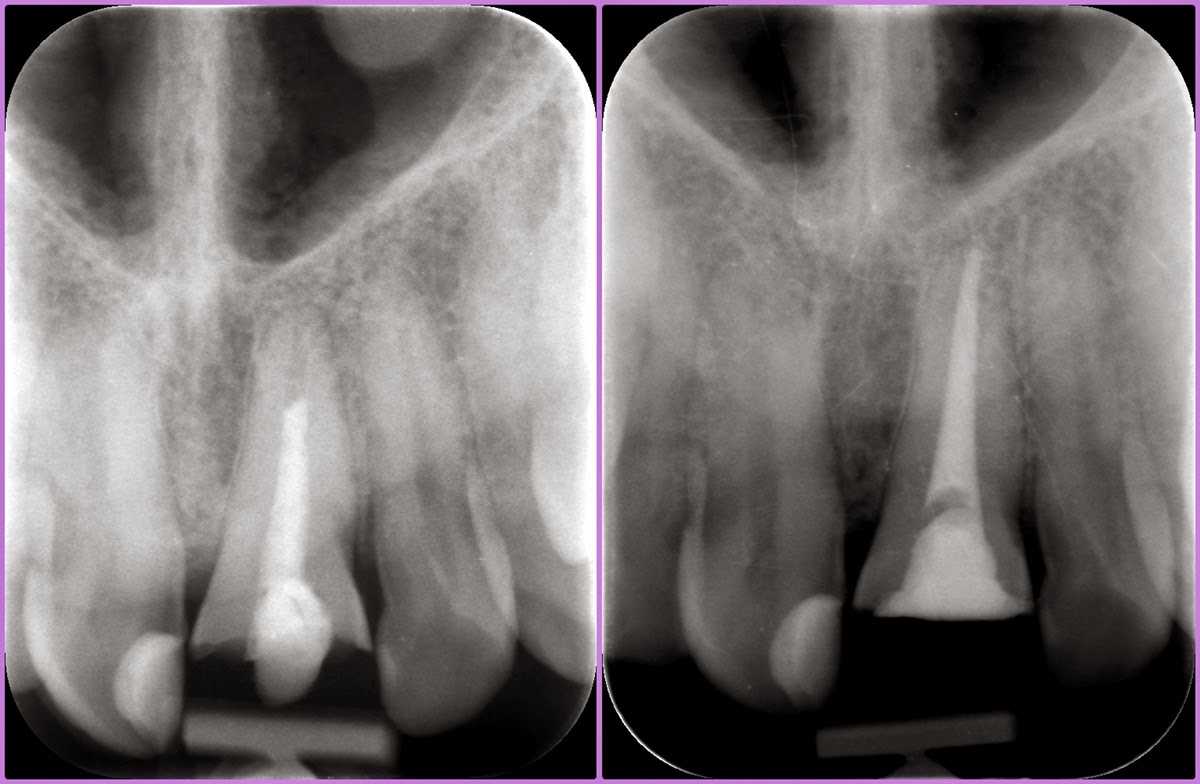

45 éves férfipáciensünk a képen látható státusszal érkezett klinikánkra. Letört és nem korrekt gyökértöméssel rendelkező bal felső nagymetszővel, illetve régi, elszíneződött töméssel bíró, formáját tekintve kedvezőtlen esztétikájú jobb felső nagymetsző foggal.

Az első feladatunk a régi gyökértömés cseréje volt, amihez gépi gyökércsatorna-tágítót és elektromos gyökércsatorna-bemérő műszert is használtunk.